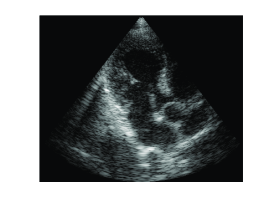

Images obtained by the proposed method, using real-valued samples per image line to perform beamforming in frequency, and by standard beamforming, using real-valued samples to perform beamforming in time, are shown in Fig. 5. Corresponding values of NRMSE and SSIM are reported in the second line of Table I. These values validate close similarity between the two methods. However, in this case NRMSE is slightly higher, while SSIM is lower, compared to the values obtained in Section III-B. Note that these values depict similarity between the signals. Differences can therefore be explained by the following practical aspect. When we obtain the set of all nonzero DFT coefficients of the beamformed signal, , all the signal energy is captured in the frequency domain. However, the signal obtained by beamforming in time, contains noise, which occupies the entire spectrum. When only the DFT coefficients within the bandwidth are computed in the frequency domain, the noise outside the bandwidth is effectively filtered out. In the signal obtained by standard beamforming, the noise is retained, reducing the similarity between the two signals.

(a)

(b)